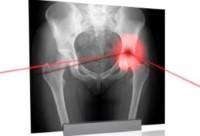

Остеохондропатия головки бедренной кости, или болезнь Легга-Кальве-Пертеса (чаще употребляется более короткое название – болезнь Пертеса), представляет собой распространенную у детей патологию тазобедренного сустава. Заболевание обусловлено нарушением кровоснабжения в области головки бедренной кости и последующим остеонекрозом…